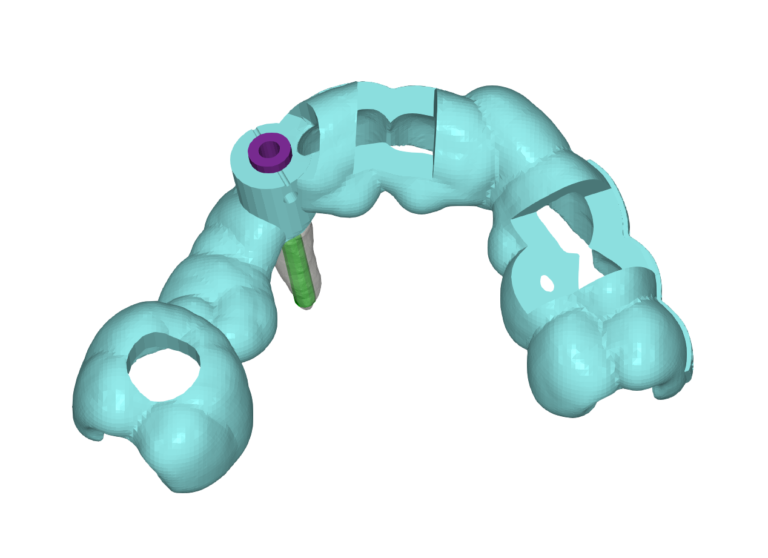

Apex Locator Guide

Due to a lack of adequate buccal bone, it is occasionally neccesary to perform Partial Extraction Therapy (PET) or the Socket Shield Technique.

These guides guide a 2mm drill to the apex of the tooth to be extracted, simplifying and speeding up the process.

Since the planning for the PET is done at the same time as the planning for the implant placement, we ensure that the socket shield will not interfere with the planned implant position.